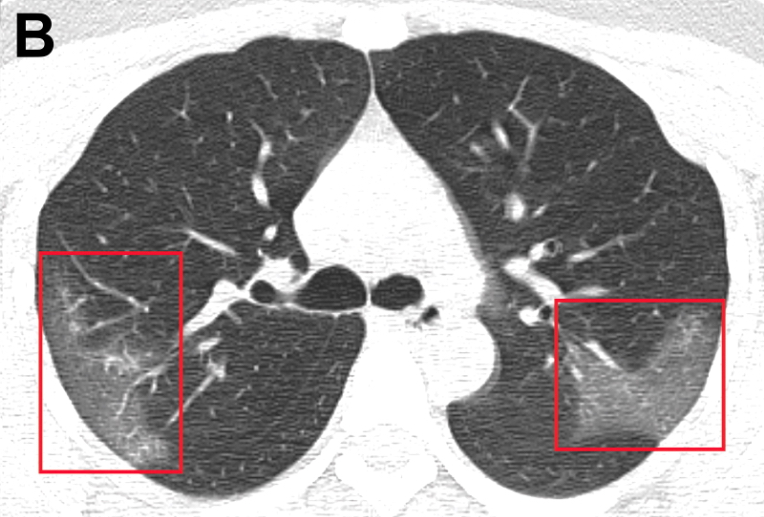

Características clínicas de los pacientes internados con neumonía por 2019-nCoV

10 febrero 2020

Cuadro febril con fatiga y tos seca, evoluciona a disnea en 5 días; presenta linfopenia, LDH elevada y tiempo de protrombina prolongado; tomografía con opacidad bilateral en vidrio esmerilado. El 26% requirió cuidados intensivo y el 4,3% falleció. JAMA, 7 de febrero de 2020